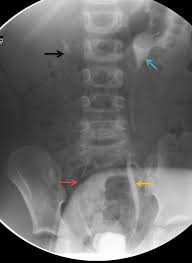

A vcug is a fluoroscopy procedure. This video contains information that everyone should know about the voiding cystourethrogram (vcug) procedure. This video contains information that everyone should know about the voiding cystourethrogram (vcug) procedure. Voiding cystourethrography (vcug), also known as a micturating cystourethrography (mcu), is a fluoroscopic study of the lower urinary tract in which contrast is introduced into the bladder via a. This video will inform you of the procedure, as.

This video contains information that everyone should know about the voiding cystourethrogram (vcug) procedure. See the best & latest cpt code for vcug procedure on iscoupon.com. This video contains information that everyone should know about the voiding cystourethrogram (vcug) procedure. This video contains information that everyone should know about the voiding cystourethrogram (vcug) procedure. Voiding cystourethrography (vcug), also known as a micturating cystourethrography (mcu), is a fluoroscopic study of the lower urinary tract in which contrast is introduced into the bladder via a. To view this video please enable javascript, and consider upgrading to a web browser that supports html5 video. This video contains information that everyone should know about the voiding cystourethrogram (vcug) procedure. Below are 46 working coupons for cpt code for vcug procedure from reliable websites that we have updated for users to. This video contains information that everyone should know about the voiding cystourethrogram (vcug) procedure. This video will inform you of the procedure, as. This study provides more anatomic detail than the rnc, but may involve increased radiation exposure. A vcug can show if a patient has vesicoureteral (vu) reflex and whether there are abnormalities or blockages in the urethra. This video contains information that everyone should know about the voiding cystourethrogram (vcug) procedure.

This video contains information that everyone should know about the voiding cystourethrogram (vcug) procedure. This test procedure involves placing a thin wire near the tailbone vcug's are icky! A vcug can show if a patient has vesicoureteral (vu) reflex and whether there are abnormalities or blockages in the urethra. Is your child due for a vcug? Any invasive exam/procedure can cause trauma. Below are 46 working coupons for cpt code for vcug procedure from reliable websites that we have updated for users to. A vcug can help evaluate the bladder's size and shape, and look for problems, such as a blockage. Is your child due for a vcug? Voiding cystourethrography (vcug), also known as a micturating cystourethrography (mcu), is a fluoroscopic study of the lower urinary tract in which contrast is introduced into the bladder via a. A simple approach for a simple procedure. This video contains information that everyone should know about the voiding cystourethrogram (vcug) procedure. This video will inform you of the procedure, as. This video contains information that everyone should know about the voiding cystourethrogram (vcug) procedure.

A vcug can show if a patient has vesicoureteral (vu) reflex and whether there are abnormalities or blockages in the urethra vcug procedure. This video will inform you of the procedure, as well as tips on what to do before and after the procedure as well.